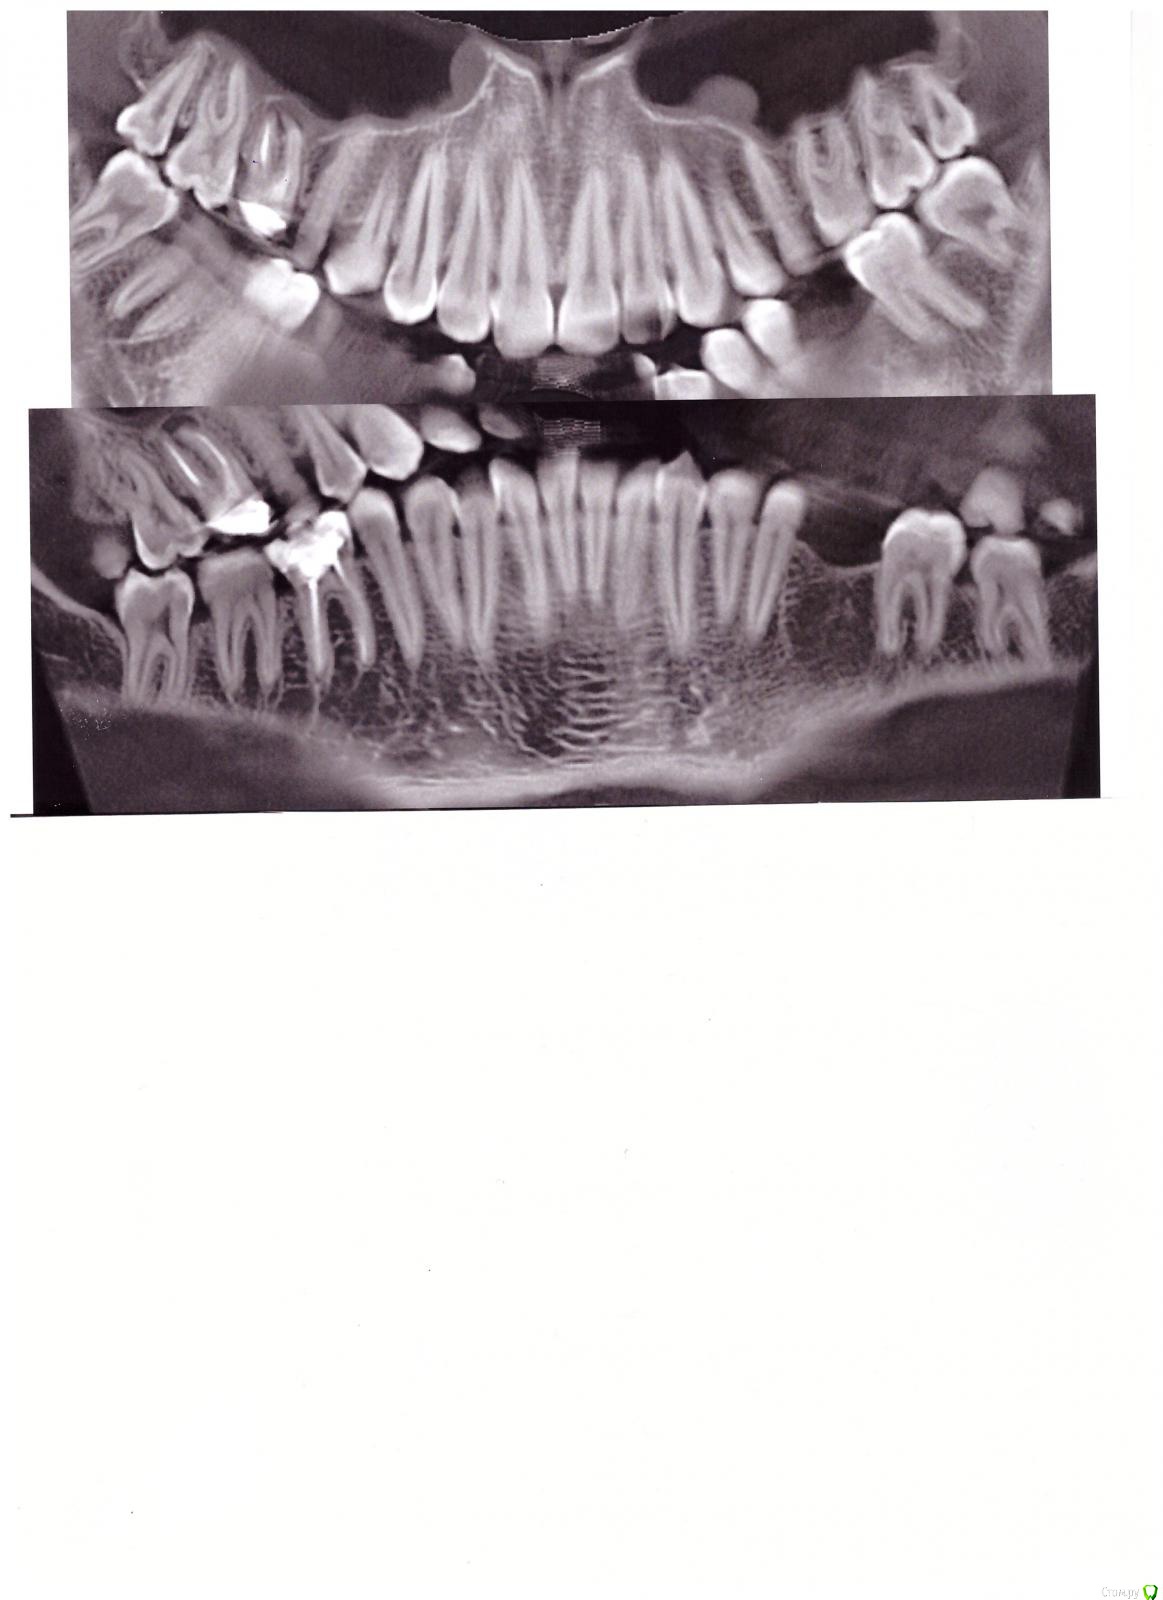

sanek2701 Опубликовано 26 июня, 2015 Поделиться Опубликовано 26 июня, 2015 (изменено) добрый вечер! недавно заметил небольшую боль при накусывании в недавно запломбированном и депульпированном зубе (6-ой снизу), о чем может говорить это? на снимке врач также рассмотрел кисту на 16 зубе под коронкой, посоветовали его удалить, или можно все таки вылечить? Изменено 26 июня, 2015 пользователем sanek2701 Ссылка на комментарий

Гарриевич Опубликовано 26 июня, 2015 Поделиться Опубликовано 26 июня, 2015 верхний правый лечите, удалять не надо Ссылка на комментарий

St. Опубликовано 26 июня, 2015 Поделиться Опубликовано 26 июня, 2015 Гарантия в медицине вообще, строго говоря, условная. При лечении каналов в том числе. Врач стремится сделать всё что от него зависит, а как Ваш организм себя будет вести никто не знает, поэтому так.Верхний(16) зуб советую пытаться лечить.По поводу нижнего расскажите подробнее - когда удаляли нерв, через сколько начал болеть, что сейчас с зубом - временная или постоянная пломба? и хотелось бы прицельный снимок нижнего зуба. Ссылка на комментарий